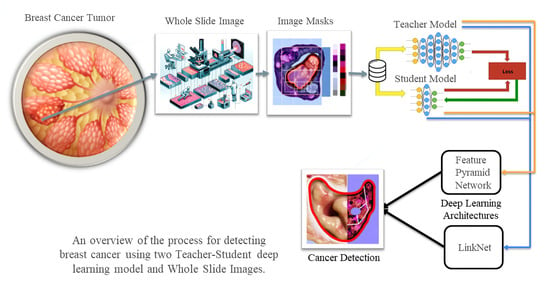

3. Methodology

3.1. Segmentation Model Training Strategy

3.3. Deep Learning Models Being Compared

3.3.1. LinkNet

3.3.2. Feature Pyramid Network